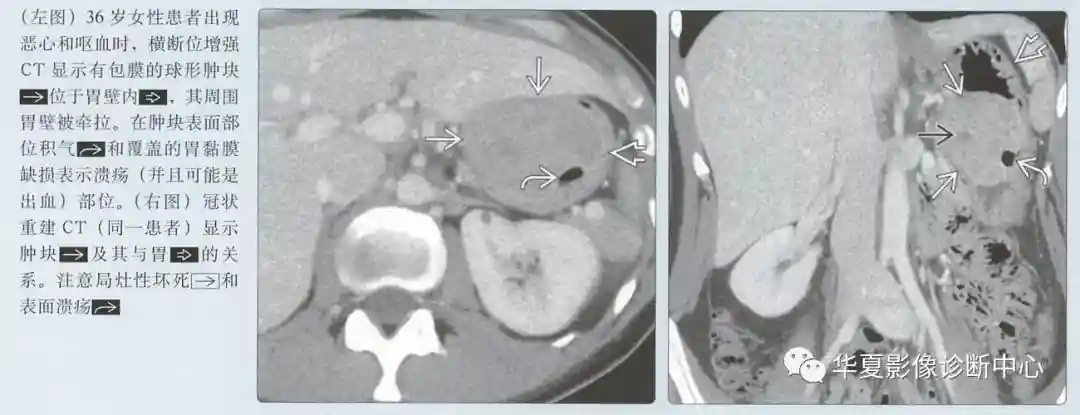

动脉期图像呈低或高血供,边界清楚的黏膜下肿块;溃疡和坏死是常见的

具有大的腔内成分的肿瘤可能类似原发性胃癌

中心溃疡常见

恶心、呕吐、体重减轻

心当胃表面和GIST溃烂时,消化道出血